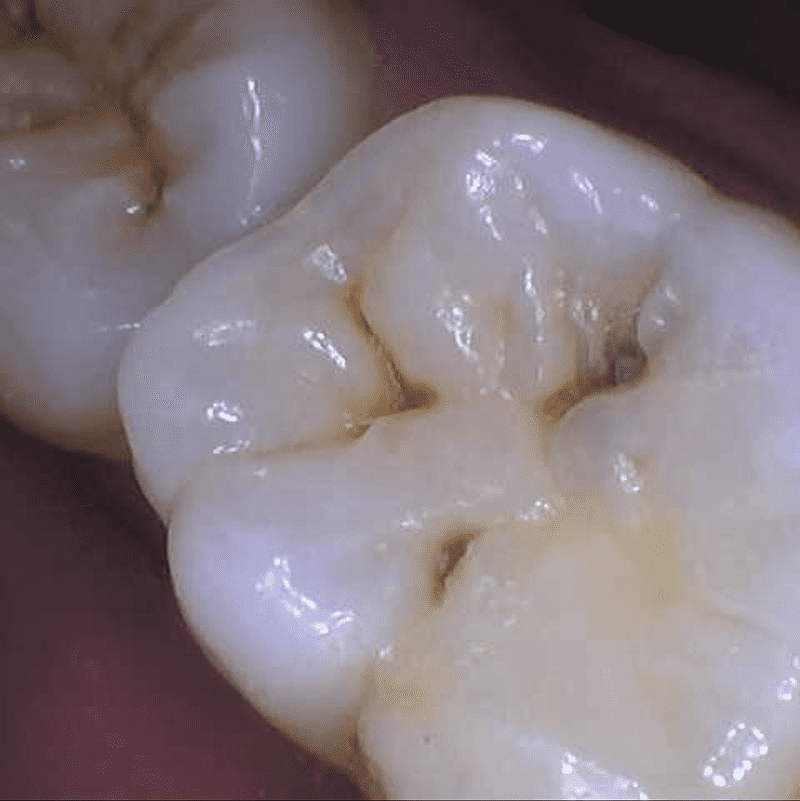

We offer state-of-the-art composite dental fillings in Leesburg, Virginia, as a core part of our comprehensive dental services. When cavities or tooth damage strike, composite fillings are a top-choice restorative solution, blending seamlessly with your natural teeth for both aesthetic and functional advantages.

- Aesthetic Appeal: These fillings are color-matched to your natural teeth, making them virtually indistinguishable. Say goodbye to unsightly metal fillings.

- A thorough examination by Dr. Kime Whitman to identify the extent of the decay or damage.

- Removal of the damaged tooth structure.

- Application of the composite material in layers, each one carefully cured to ensure a solid bond.

- A final shaping and polishing to create a seamless appearance.